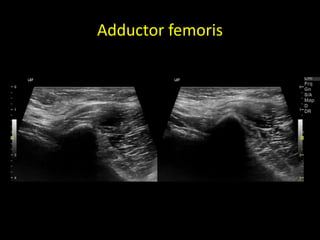

Adductor femoris

The Doha Agreement2014 Groin Pain (GrP) • Excluding Lower Abd. & Uro-Gynaecological causes • Excluding hernias • Excluding intra-articular disorders – Adductor related GrP – Ileopsoas related GrP – Inguinal related GrP • No inguinal hernia is present • Aggravated pain during ”sit-up” test or Valsalva – Pubic related GrP • Pain in the symphysis or adjacent bone

Pubalgia athletica -sports hernia